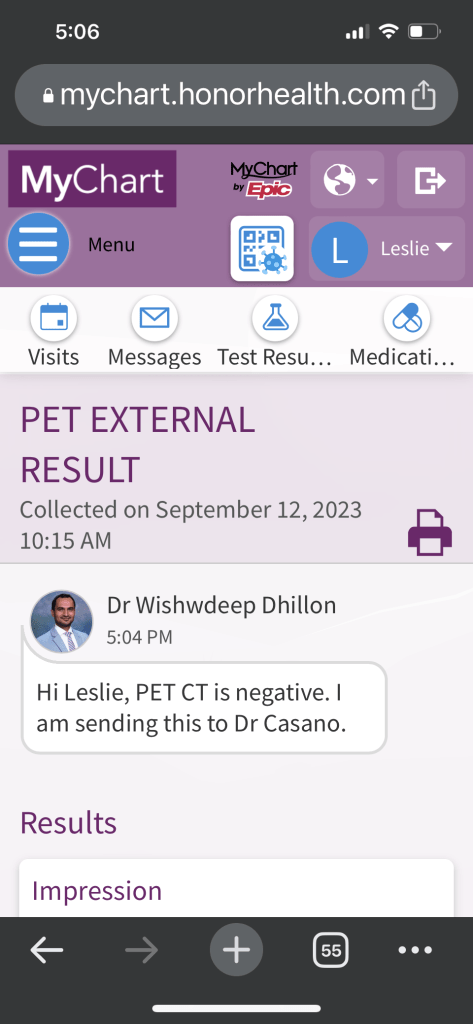

Tuesday, September 12th

Hey family, I had my PET scan this morning. It usually takes 2 days to get the results back, but I got a message less than 2 hours later that my results had been posted.

It had a lot to say, lots of jargon. It said the spot we've been working on has not shrunk, so that's a bummer, but it also said it is no longer considered malignant. Nothing lit up as cancerous. So that's really good news! I won't feel like it's entirely over until I can keep my scans clean for the next 4.5 years, but this is a good start.

Does this look like the kind of "clean scan" report YOU would have envisioned? Me neither. My oncologist's summary was much simpler, but still not quite what I had imagined: